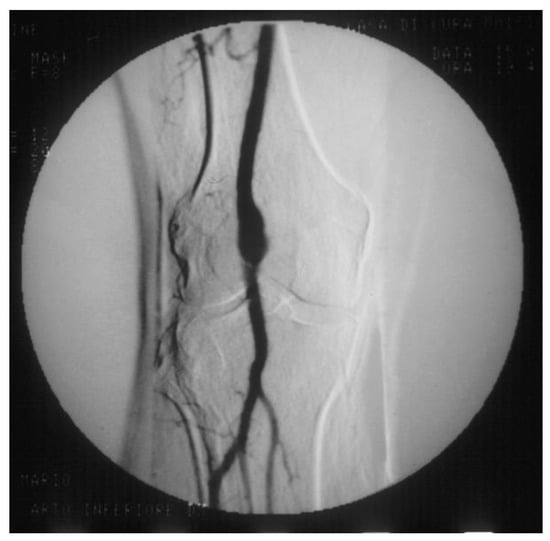

PAAs should be detected not so much for the risk of rupture, which is rare, but for their risk of embolization and thrombosis. The physiologic flexion of the knee can act as a tremendous stress for the parietal thrombus of the PAA, potentially causing paroxysmal, multiple, and insidious episodes of asymptomatic microembolization to the tibial arteries (Figure 11). As a consequence, the latter can progressively obstruct, drastically reducing the run-off of the popliteal artery and giving rise to a clinical picture ranging from blue toe syndrome, or LEAD with IC up to chronic limb-threatening ischemia. PAA can also thrombose entirely due to the affected tibial out-flow, so it manifests itself with ALI: limb loss can reach 14% in these patients [66,67].

Figure 11. Arteriography showing popliteal artery aneurysm. The physiologic flexion movement of the knee can dislocate part of the mural thrombus, which embolizes and occludes some tibial arteries, giving rise to clinical pictures ranging from an asymptomatic state to intermittent claudication, or chronic limb-threatening ischemia, or acute limb ischemia.